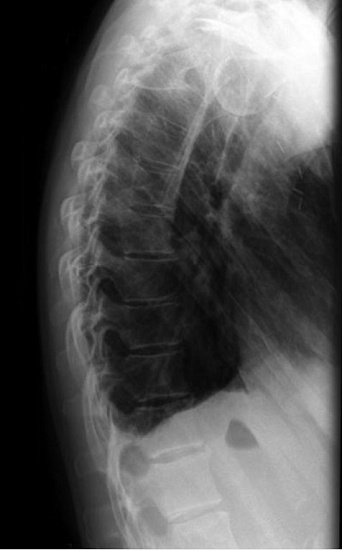

Рентгенография органов грудной клетки – распространенный метод скринингового исследования органов грудной клетки.

1. Рентгенография органов грудной клетки в 2-х проекциях - скрининговое исследование органов грудной клетки, выполняемое в двух проекциях.

2. Рентгенография легких в прямой проекции – скрининговое исследование органов грудной клетки, выполняемое в двух проекциях.

3. Прицельная рентгенография органов грудной клетки – исследование позволяет оценить наличие воспалительных, травматических, опухолевых, профессиональных (силикатоз, асбестоз) изменений легких.